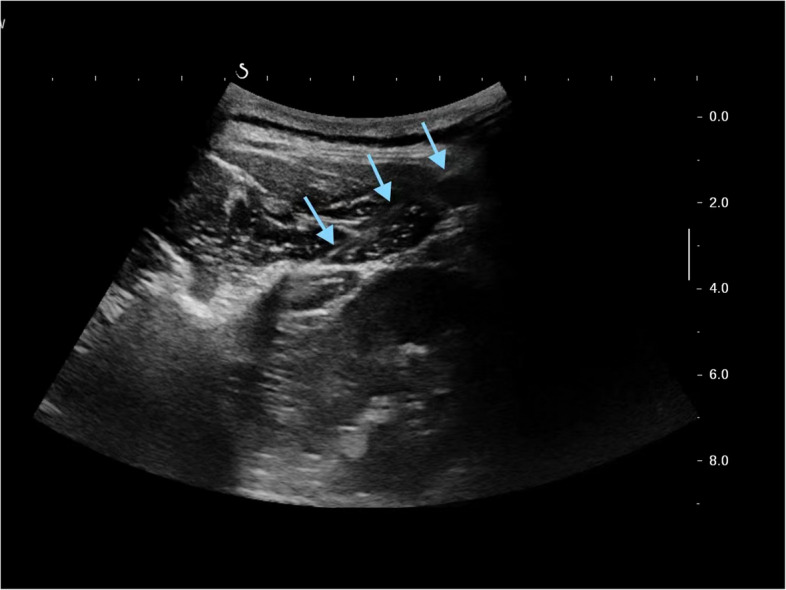

Introduction: Non-specific low back pain (NLBP) is increasingly prevalent in the world due to changes in lifestyle and work habits. It is found that the symptom is usually associated with damage in the thoracolumbar fascia (TLF) and its surrounding muscles. This paper introduces a pioneering approach for treating NLBP, using the heterogeneous echo zones on ultrasound images as needling targets, presenting a novel treatment protocol.

Methods: An open randomized controlled trial is designed and conducted, in which 48 patients with NLBP will be randomly allocated at a ratio of one to one to an ultrasound-guided acupuncture (UGA) group and a regular acupuncture treatment (RA) group. The trial involves a 3-week treatment along with a follow-up for 3 weeks. Its primary purpose is to evaluate the feasibility and safety of ultrasound-guided acupuncture in the TLF and its adjacent muscles as a treatment method for NLBP. As its secondary objective, the treatment effectiveness will be assessed by observing the changes in the patient's pain level and low back dysfunction before and after treatment. The ultrasound-related parameters and adverse events will also be collected.